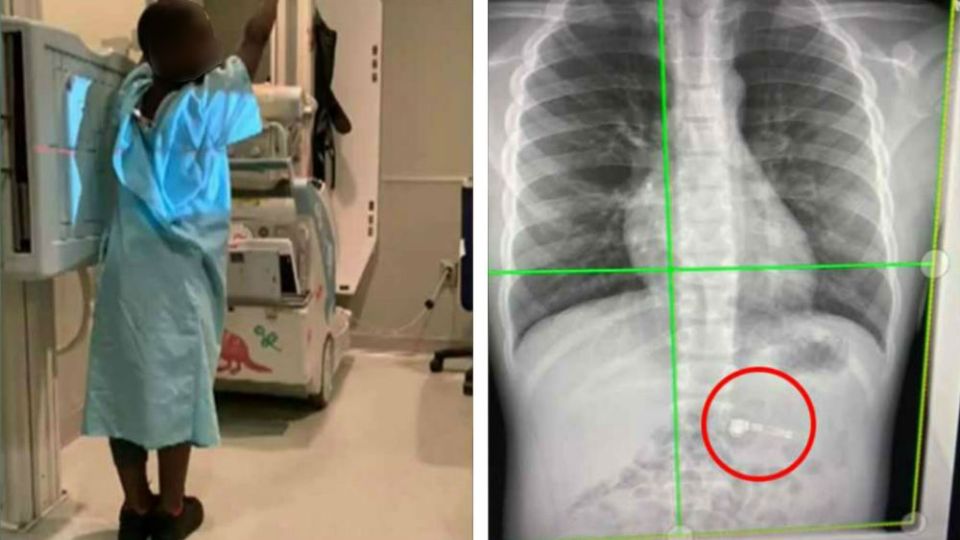

Llevan a niño a hospital, ¡se tragó su regalo de Navidad!

por Redacción AM2 enero, 2020